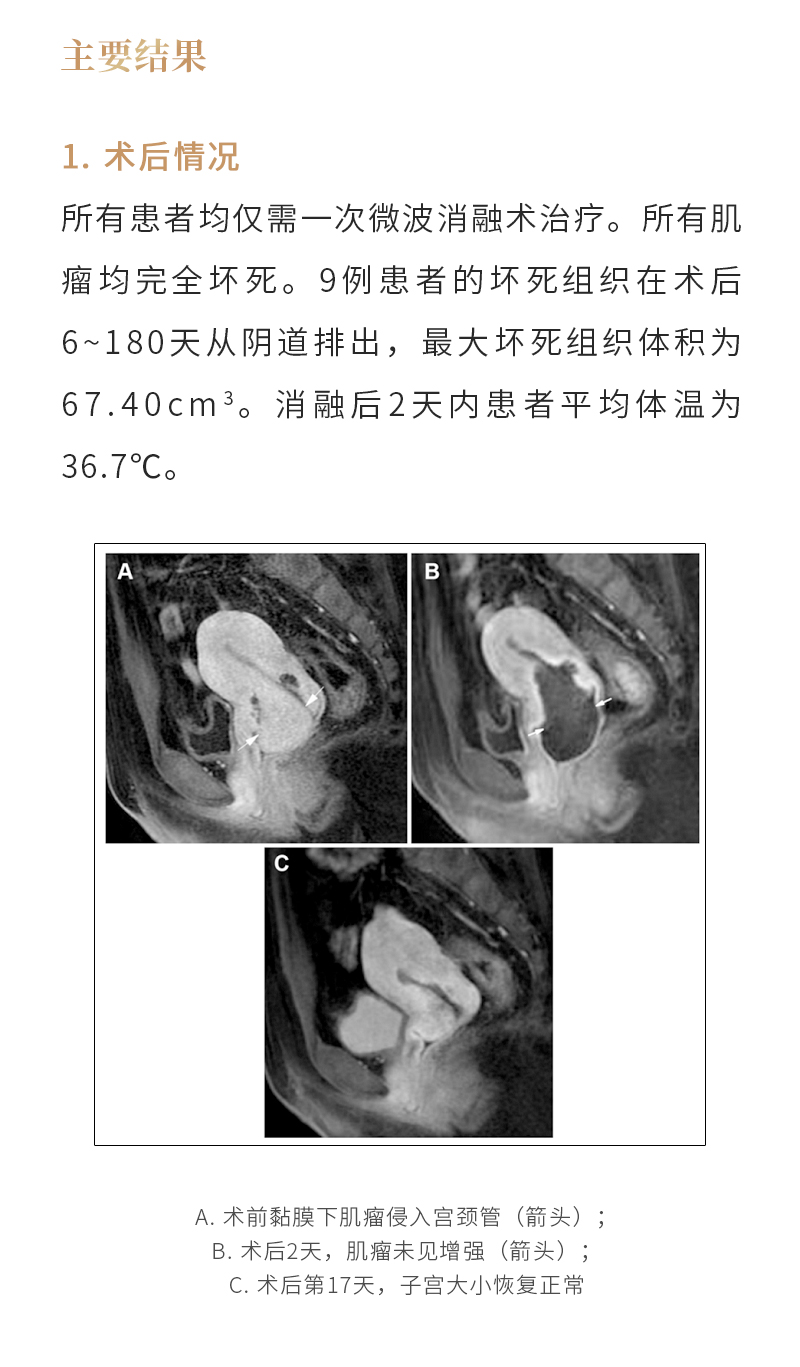

消融治疗子宫肌瘤——【海杰亚科研资讯】第260期